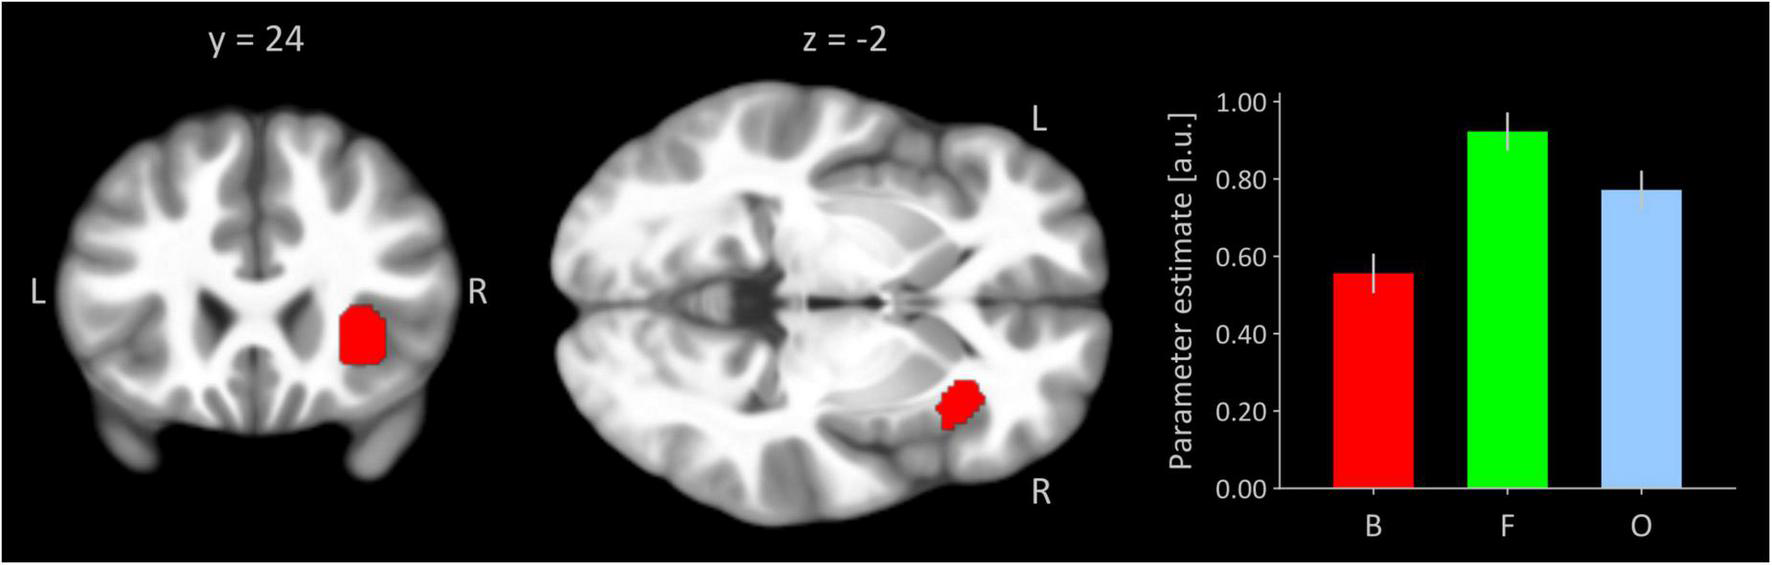

Figure 1 shows the right insular seed region from the present task-based activation analysis inferred by a significant quadratic trend testing for an invU activation pattern. This trend is demonstrated by the inserted bar graph depicting cluster-averaged, estimated neural activation for conditions of boredom, flow, and overload for the seed. The cluster size was 280 significant voxels, and the peak voxel was located at MNI-coordinates [38, 24, −2] (z-value = 6.55, p(FWE) < 0.001).

FIGURE 1

Right anterior insular seed region functionally defined by invU-shaped activation effect at a significance level of p < 0.05, whole-brain FWE-corrected. Cluster is overlaid on coronal and transversal sections obtained from participants’ MNI-normalized and averaged T1 images (N = 41) using MRIcroGL (Rorden and Brett, 2000). L, left; R, right. The bar graph depicts cluster-averaged estimated neural activation for conditions of boredom (B), flow (F), and overload (O); the error bar is the standard error of mean (N = 41).